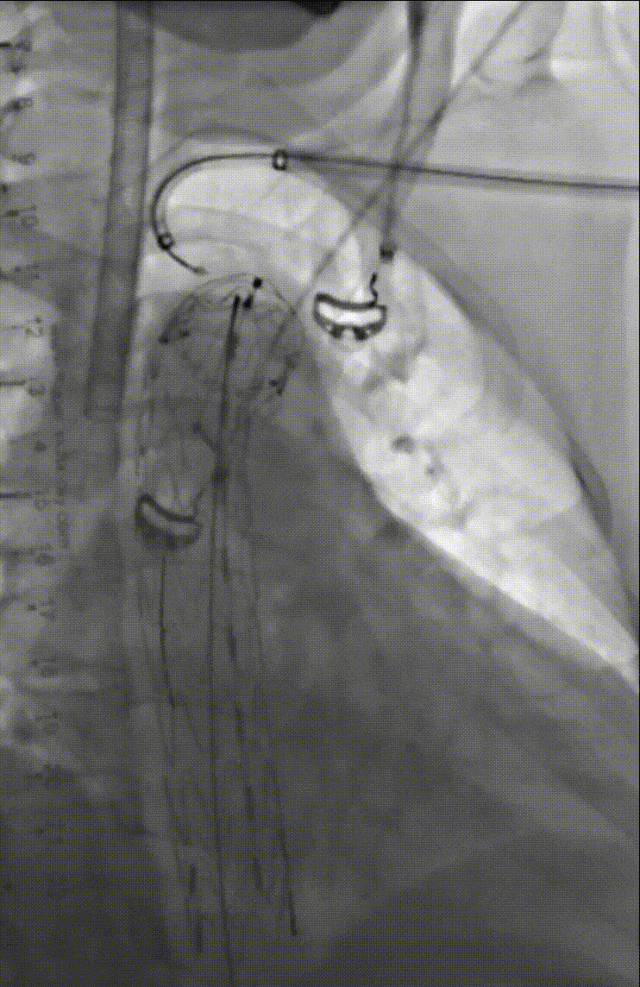

技术应用:这是一例夹层+迷走右锁骨下+单发左椎动脉+卡梅尔憩室的病例,通过TEVAR+LSA-LCCA转流+单发LVA-LCCA转流+迷走RSA-RCCA搭桥解决分支重建问题,远期效果良好。

AD+迷走RSA+单发LVA+KD